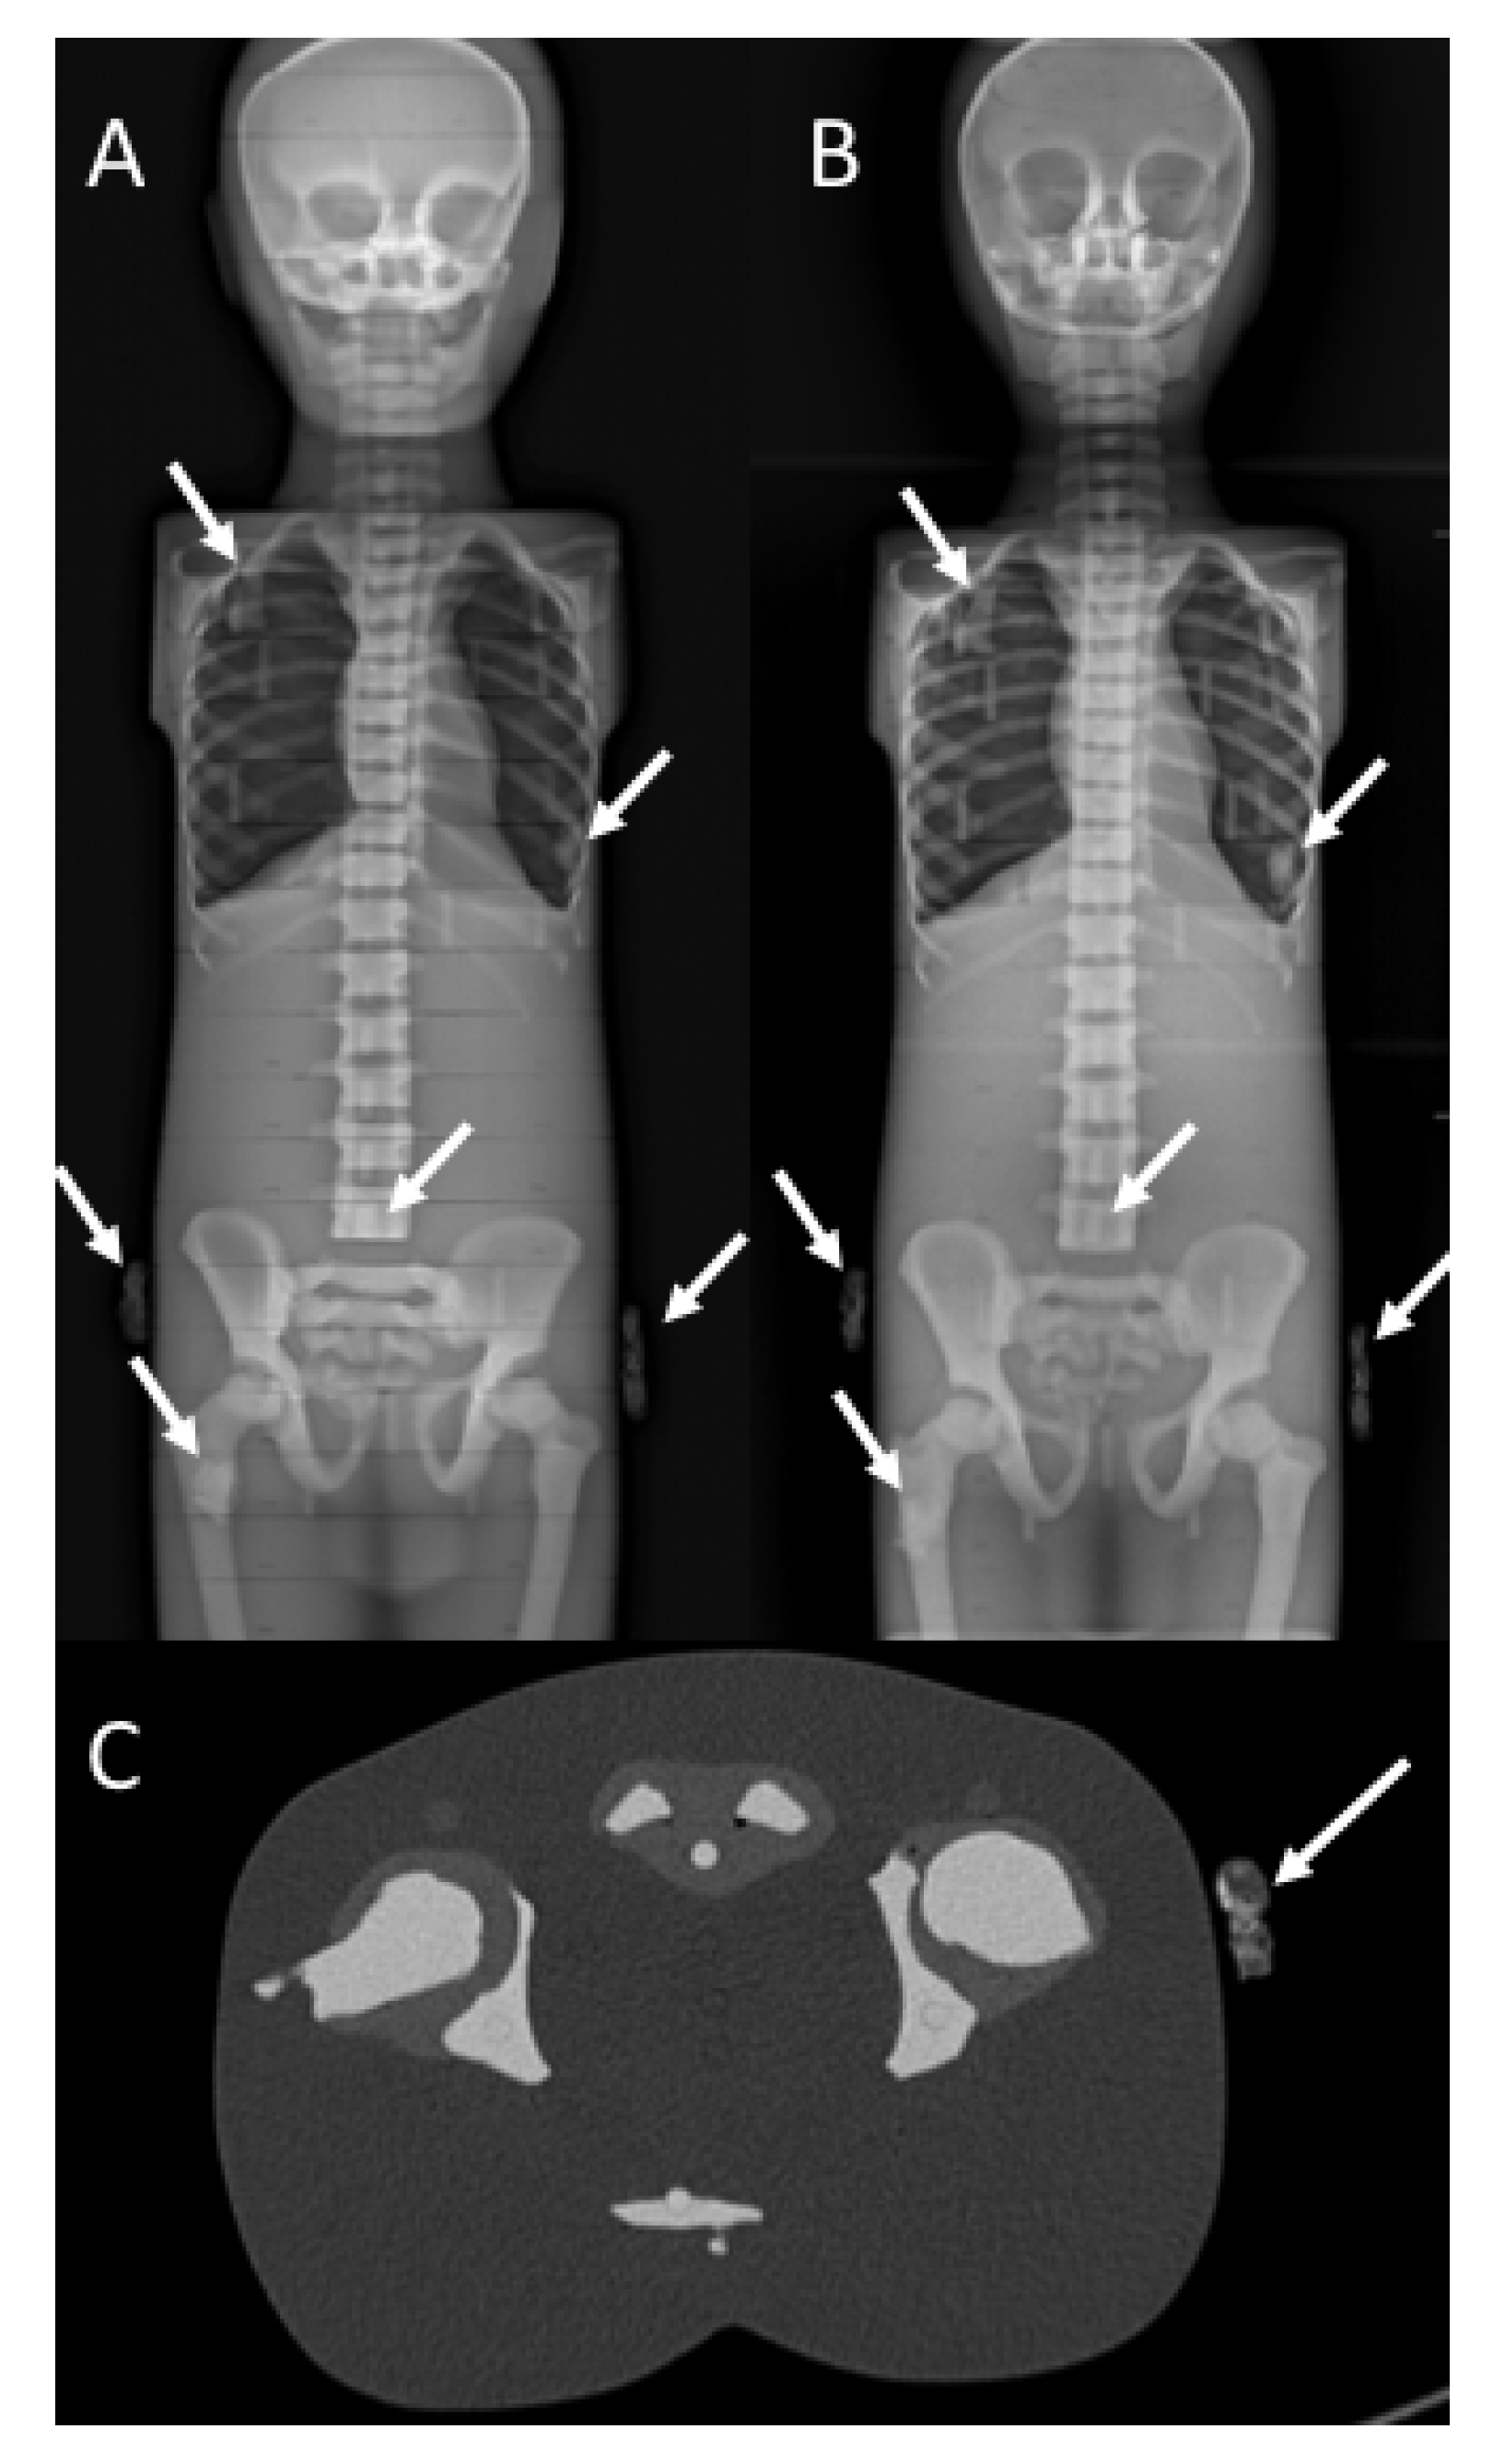

Intermodality reliability, quantified as the mean of the difference between the two modalities’ measurements (bias) and the repeatability coefficient (CoR), showed excellent agreement for EOS, conventional radiography, and CT with a bias calculated to be 0.14 mm (88% reproducibility; CoR 2.9; 95% CI from −2.8 to 3.1 mm; p = 0.5) and 0.15 mm (81% reproducibility; CoR 5.2; 95% CI from −5.5 to 5.2 mm; p = 0.7) when comparing EOS to conventional radiography and CT, respectively. The assessment of interobserver reliability in the EOS modality showed 71% reproducibility between different observers, with a bias as low as 0.6 mm (CoR 7.2; 95% CI from −6.6 to 7.8 mm; p = 0.25) (Figure 1).

Figure 1. Intermodality and interobserver reliability of insert length measurements among different modalities and among different observers: (A) Intermodality reliability between EOS imaging system and computed tomography (CT) scanning. The mean of the measurements obtained with EOS and CT for each insert is reported on the x-axis; the difference between the two measurements is reported on the y-axis. (B) Intermodality reliability between the EOS imaging system and conventional X-ray. The mean of the measurements obtained with EOS and X-ray for each insert is reported on the x-axis; the difference between the two measurements is reported on y-axis. (C) Interobserver reliability between measurements obtained by two different observers with the EOS imaging system. The mean of the measurements is reported on the x-axis; the difference between them is reported on the y-axis.